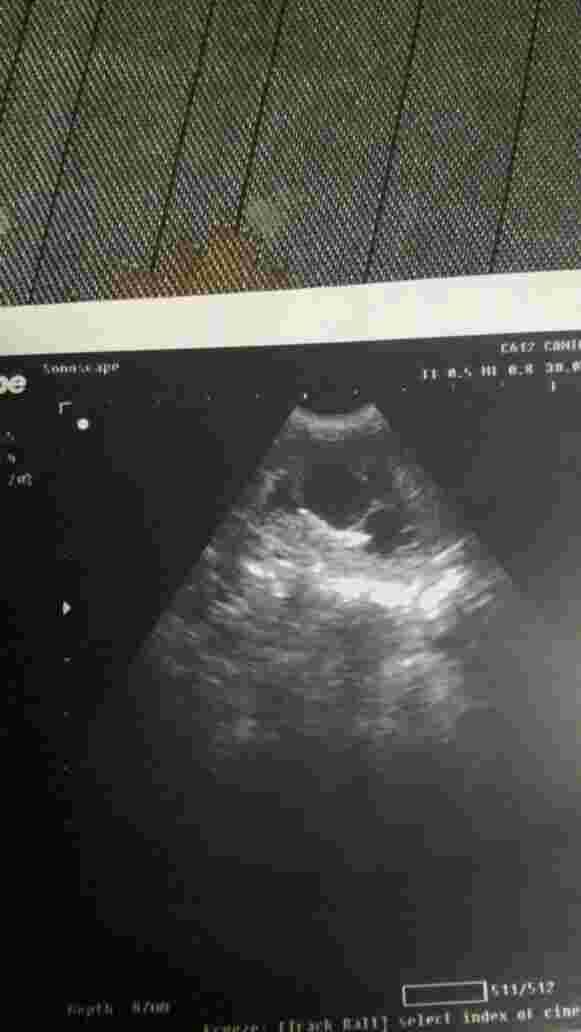

hello yesterday i went to the vet after my cat lost weight he told me that my cat suffers from kidney failure now he has one kindey that works but not with high efficiency and the other one stopped completely now my cat refuses to eat or drink what should i do and how long can he live by one kidney? a picture of his kidneys below

Kidney failure is common amongst cats and the survival time varies based on the underlying cause of the kidney failure. A full report of what was found on the ultrasound would help here; because just an image of the kidney itself isn't enough to make a diagnosis as to why the 1 kidney is no longer working nor can we predict how long he can live based on this. The only thing that can be gathered based on the photos you have sent is that there is hydronephrosis (distension of the kidney with fluid) of one of the kidney's which leads to severe malfunction . More importantly, since your cat is refusing to eat, he needs to be hospitalized and given IV fluids, force feeding (by means of a tube if necessary) and pain medication. He will not be able to survive long if he does not eat. Once he is able to be stabilized (by eating on his own), then you can try to manage his condition at home with subcutaneous fluids and a prescription kidney diet (i.e. Hill's K/D, Royal Canin renal). However, the condition that he has is severe and survival is going to be tough for him, especially since one of his kidney's is in such bad shape. I send all my best to both you and your cat. I hope he gets better soon. Take care.